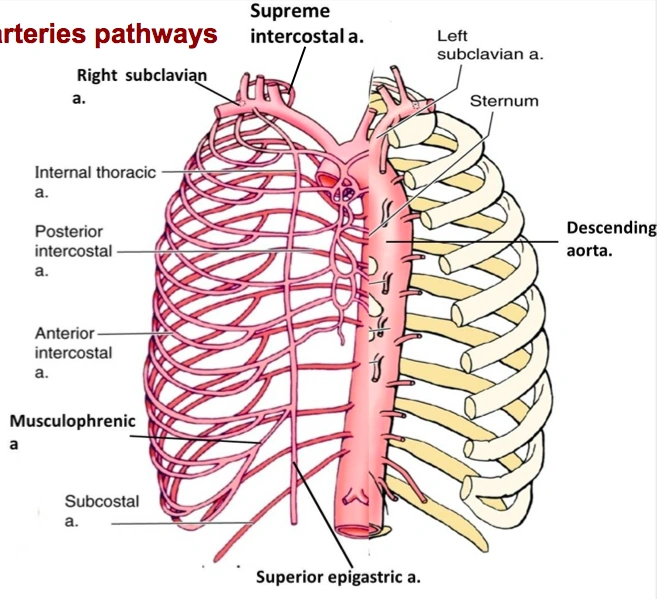

- Blood supply to the rib cage originates from what 2 places?

- what 2 arteries supply the intercostal spaces of the rib cage

- what branch off of the subclavian artery goes down specifically to the diaphragm?

aorta and subclavian artery

Anterior and posterior intercostal arteries

notice how branches from the aorta go around and supply the rib cage

the internal thoracic artery

look at picture

study picture

Identify/describe the intercostal artery pathway?

- Intercostal arteries/veins run in the ___________ aspect of

the intercostal space?

- They are ________ to the “superior rib” of the intercostal space?

- Collateral branches of intercostal arteries/veins run in the _________ aspect of the intercostal space

superior aspect

inferior

inferior

go back and rememeber the subclavian artery and how it had the VA, the thyrocervical trun and the costocervical trunk.....one branch from the costcervical trunk that went up to the skull was the deep cervical artery....what is the branch of this trunk that goes down?

what then branches from the artery?

the supreme intercostal artery

the 1st and 2nd posterior intercostal arteries

notice the subclavian, the costcervical trunk and the deep cervical artery and the supreme intercostal artery...then notice how it splits off into 2 branches under the clavicle

the 3rd through the 11th intercostal arteries branch off from what?

notice it in the picture?

from the aorta

Posterior intercostal arteries:

- There are only 11 “posterior intercostal arteries” that supply what?

- The ________ which arises from aorta helps supply what as it runs inferior to the rib?

the 11 intercostal spaces

subcostal artery

the 12th rib

notice how in the picture you can see the subcostal artery down below the ribs as it branches from the aorta

Anterior intercostal arteries:

- These arteries branch from where?

- then this originates from where?

internal thoracic artery

- Internal thoracic artery originates from subclavian artery

the internal thoracic artery comes from the ____________ vein and then runs behind the anterior ________?

subclavian vein

anterior sternum

notice the internal thoracic artery coming down right near the sternum

The Anterior intercostal arteries supply which intercostal spaces?

- The lower intercostal spaces supplied by what?

1-9

posterior intercostal arteries

notice how the intercostal arteries run superior and inferior in the intercostal spaces

look at all the arteries and their relationship

look at how the posterior intercostal arteries come from the back and wrap around the intercostal spaces from the back

look at picture